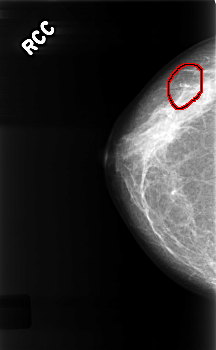

FILE: C_0335_1.RIGHT_CC.OVERLAY

TOTAL_ABNORMALITIES 1

ABNORMALITY 1

LESION_TYPE CALCIFICATION TYPE FINE_LINEAR_BRANCHING DISTRIBUTION LINEAR

ASSESSMENT 4

SUBTLETY 4

PATHOLOGY BENIGN

TOTAL_OUTLINES 1

BOUNDARY